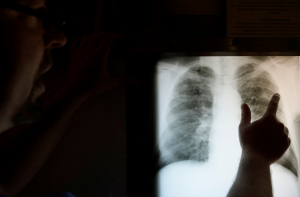

В своей публикации на сайте Sūdzības.lv мужчина пишет, что у него были подозрения на перелом ребер.

«Сидим с подозрением на сломанные ребра уже четвертый час. Ждем травмотолога. Сделали рентген. Неужели здесь нет никого, кто мог бы его проанализировать? Понимаю час, полтора, но четыре - это уже многовато. Никто даже не может сказать, когда врач вообще появится на работе. Если бы мы знали, что ничего серьезнее перелома ребер нет, могли бы пойти домой», - пишет мужчина.

Пользователи в комментариях, между тем, заметили, что перелом ребер не является вопросом жизни и смерти, и, возможно, кто-то нуждался в помощи более остро, чем он.